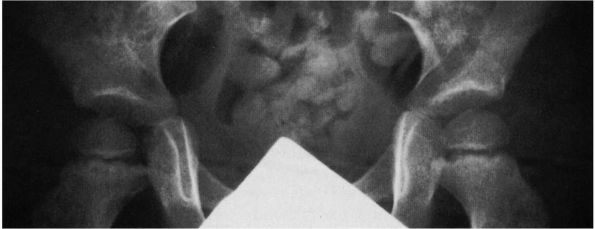

refers to inadequate development of the acetabulum, femoral head, or

both. All subluxated hips are by definition dysplastic.

Radiographically, however, the major difference between dysplasia and

subluxation is the intactness of the Shenton line (Figure 15-7).

In subluxation, the Shenton line is disrupted, and the femoral head is

superiorly or laterally displaced from the medial wall of the

acetabulum. In dysplasia, the normal Shenton line relation is intact.

![]() |

|

FIGURE 15-7.

Radiographically, the major difference between dysplasia and subluxation is the intactness of the Shenton line. The right hip is dysplastic (Shenton line intact). The left hip is subluxated (Shenton line disrupted). All subluxated hips are, by definition, dysplastic. (Weinstein SL. Natural history of congenital hip dislocation [DDH] and hip dysplasia. Clin Orthop 1987;225:62-76) |